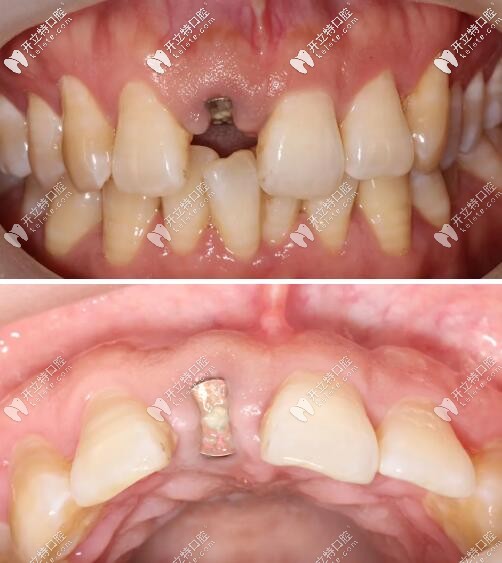

口內(nèi)檢查

被磕的11號(hào)牙(門牙)切端1/3折斷,并見不規(guī)則縱向裂紋;

牙齦色粉、質(zhì)韌,無明顯紅腫,牙齦乳頭充盈。

術(shù)后三個(gè)月復(fù)查見近遠(yuǎn)中齦乳頭高度維持良好,唇側(cè)較豐滿。

門牙外傷即刻種植牙三個(gè)月后